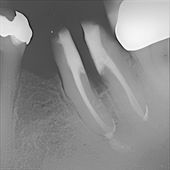

Hier sehen Sie den gleichen Zahn einige Wochen später nach erfolgreicher Aufbereitung der Nervenkanäle, sorgfältiger Desinfektion des Inneren der Wurzeln, Ausheilung der Knochenentzündung und Abheilung der Fistel nach erfolgreicher Wurzelfüllung bis zu den Wurzelspitzen. Der dunkle Bereich der Knochenentzündung aus dem ersten Bild ist verschwunden. Der Zahn ist wieder völlig fest. Man sieht aber, dass Wurzelfüllungsmaterial aus dem Zahn zwischen die Wurzeln gelangt ist. Das ist ein deutliches Zeichen dafür, dass sogar der Zahnboden bereits zerstört war.

Hier sieht man den gleichen Zahn kurz vor der Abdrucknahme für eine Doppelkrone. Die beiden Wurzeln wurden behutsam voneinander getrennt (wir nennen das "Hemisektion"), um den Bereich zwischen den Wurzeln für die notwendige Zahnreinigung durch den Patienten zugänglich zu machen. Der stark erkrankte Zahn konnte durch diese schonenden, konservierenden Maßnahmen langfristig erhalten werden. Ein nach einer Extraktion notwendiger Zahnersatz in Form einer Brücke oder eines Implantates konnte erfolgreich vermieden werden.